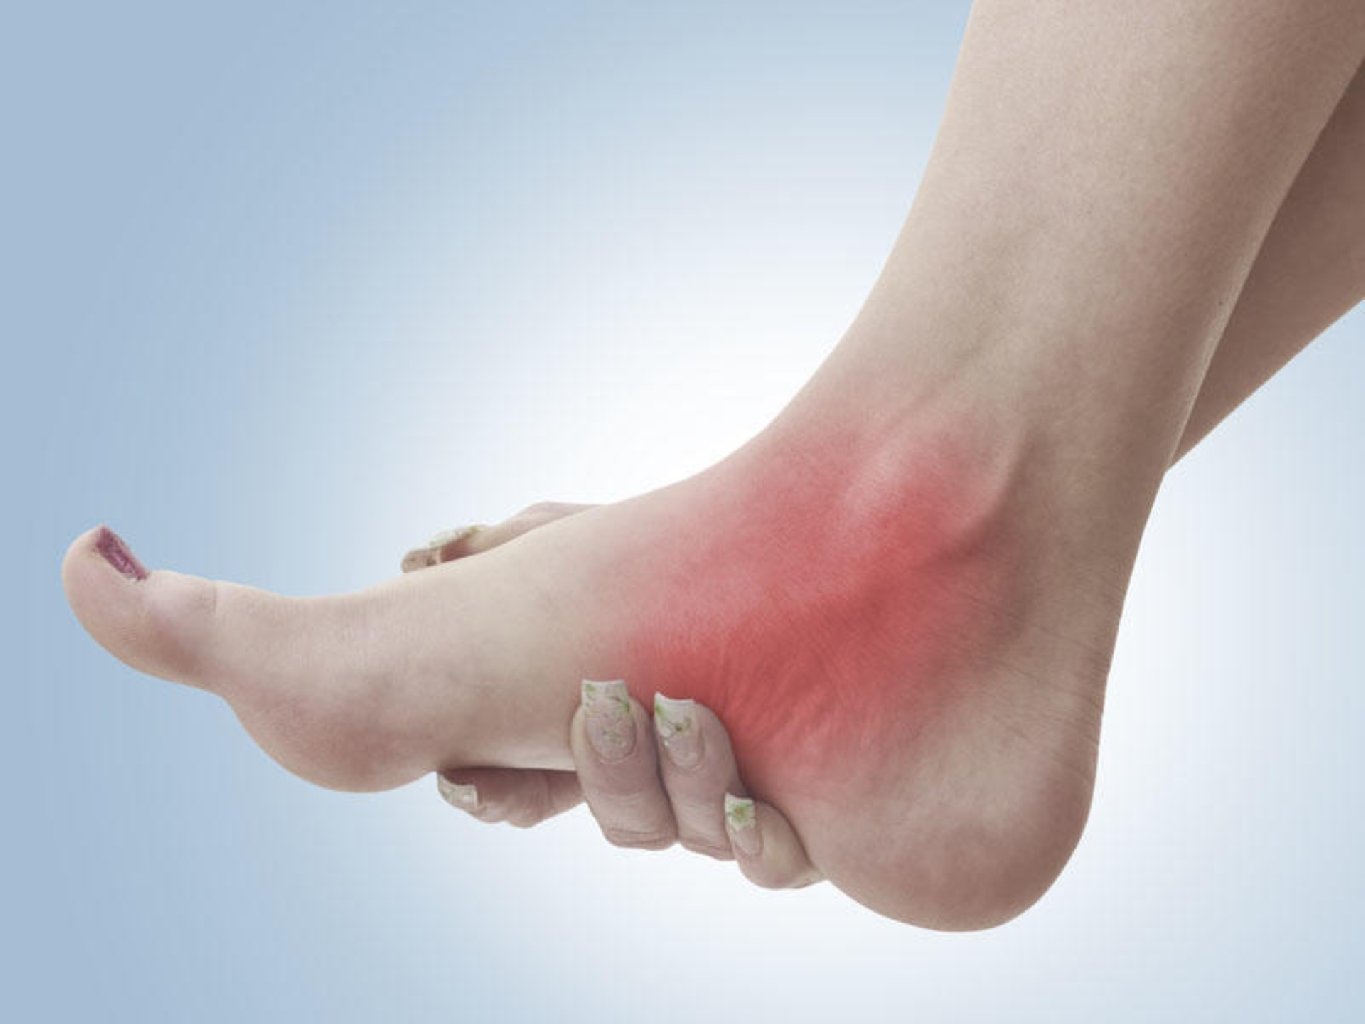

Simptomlar: Oynaq Ağrısı və Şişkinlik: Bir və ya bir neçə oynaqda ağrı və şişkinlik yarana bilər. ...

1. Səbəblər: Travma: Düşmə, idman xəsarətləri və ya qəzalar kimi travmatik hadisələr oynaqların ç ...